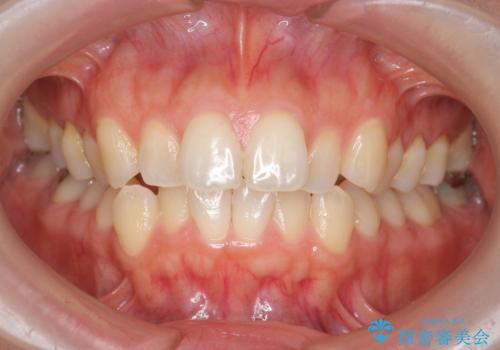

[ インビザライン矯正 ] マウスピースで治す前歯のがたつき

担当医 大元洋佑

![[ インビザライン矯正 ] マウスピースで治す前歯のがたつきの症例 治療前](https://seimitsushinbi.jp/wp/wp-content/uploads/2023/11/C7-500x350.jpg?v=1699665009)

![[ インビザライン矯正 ] マウスピースで治す前歯のがたつきの症例 治療後](https://seimitsushinbi.jp/wp/wp-content/uploads/2023/11/IMG_2993-500x350.jpg?v=1699664953)